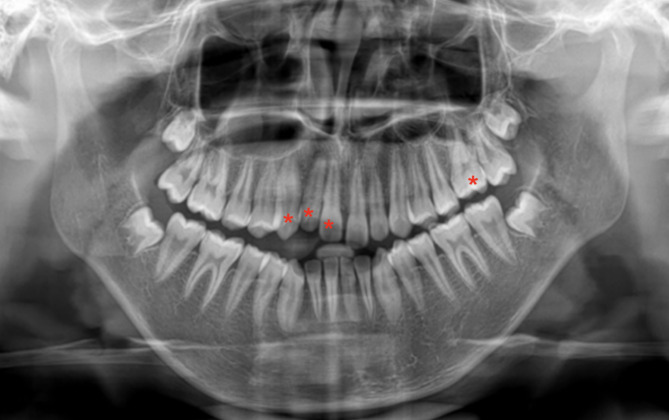

A panoramic radiograph revealed that the impacted teeth’ roots were well-developed, with no physical barriers such as dental tumors, cysts, etc. (Fig. 2). CBCT showed no radiolucencies around the root apices of the #11,#12,#13,#26. The periodontal membrane space is clear and complete, with no signs of ankylosis (Fig. 3). The normal percussion result further ruled out the possibility of ankylosis.

Fig. 2.

Pretreatment panoramic radiograph